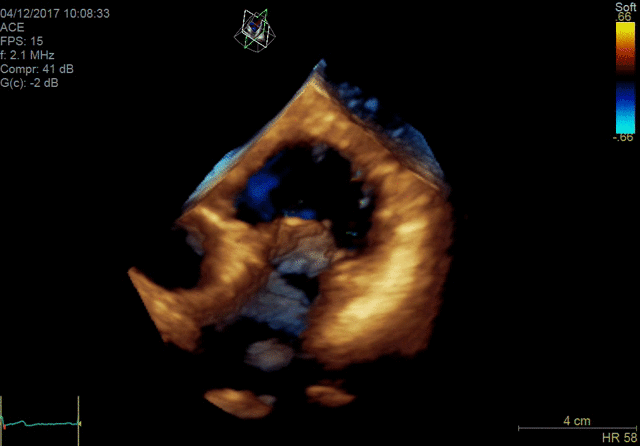

Vivid E95